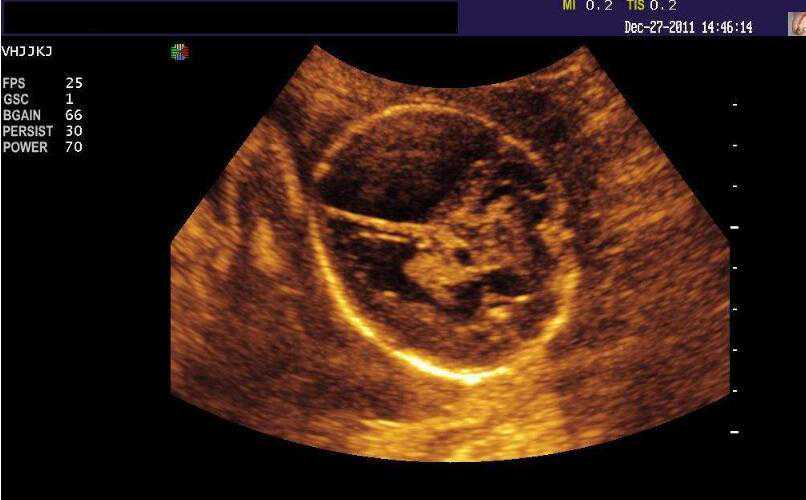

现在的医学技术已经很发达了大部分的病情都可以有效的治疗,就算是怀孕时孩子的情况也能看的一清二楚,很大的程度上避免了的畸形儿的出生,所以现在的人也都很依赖和信任医生。

大部分的情况下,只要在产检的时候一切都是正常的,那么在出生的时候就是健康的,所以很多的人都认为,只要检查的时候是没事的,那么孩子出生后也是没事的。

不过的凡事都是有例外的,并不是所有的畸形都可以在孕期的时候检查出来,这几种情况,就是一些例外,在产检的时候也无法发现。